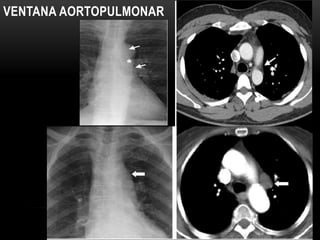

VENTANA AORTOPULMONAR

• #20 Radiografía y TAC.— una concavidad focal en el borde izquierdo del mediastino por debajo de la aorta y por encima de la arteria pulmonar izquierda puede verse en una radiografía frontal (fig. 5). Su apariencia puede ser modificada por tortuosidad de la aorta. La ventana aortopulmonar es un lugar común de linfadenopatía en una variedad de enfermedades inflamatorias y neoplásicas.The aortopulmonary (AP) window is a middle mediastinal space bounded superiorly by the inferior margin of the aortic arch; inferiorly by thesuperior margin of the left pulmonary artery; anteriorly by the posterior wall of the ascending aorta; posteriorly by the anterior wall of the descending aorta; medially by the trachea, left main bronchus, and esophagus; and laterally by the left lung (7). The AP window contains lymph nodes, the left recurrent laryngeal nerve arising from the vagus nerve, the left bronchial arteries, the ligamentumarteriosum, and fat.IMAGEN DOS:AP window lymphadenopathy. (a) Chest radiograph shows the AP window with an abnormal convex border (arrow). (b) CT scan demonstrates lymphadenopathy (arrow), which accounts for the distortion of the AP window in a.